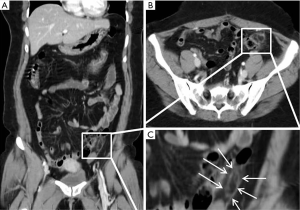

A 35-year-old female presented with acute left lower quadrant abdominal pain. The pain is described as moderate in severity, achy in nature. The patient reported associated nausea. The patient was found to have elevated white blood cell count in the ED. The working differential diagnosis at the time was diverticulitis or colitis. A CT scan obtained demonstrated an oval fat density with subtle hyperattenuating center (Figure 2).

On CT study, acute epiploic appendagitis consists of an oval lesion with fatty tissue attenuation that is commonly 1.5–3.5 cm in diameter, but no larger than 5 cm, lying adjacent to the anterior surface of the colon wall (7). The lesion is surrounded by a hyperattenuating ring, reflective of inflammatory changes. A central high attenuation region indicating venous thrombosis is frequently visualized (7). Occasionally, inflammation will cause parietal peritoneum thickening (1,7). Acute epiploic appendagitis rarely causes colonic wall thickening or occurs in hernia sacs, although Singh et al. documented the first case within an incisional hernia sac in 2004. Although symptoms should subside within weeks, CT changes are slower to occur, but will resolve by 6 months (20-22). Ultrasound imaging at the point of maximum tenderness will demonstrate an oval non-compressible hyperechoic mass, circumscribed with a hypoechoic rim, abutting the colon wall (22-24). The color Doppler will indicate no central blood flow (24,25). Although acute epiploic appendagitis can be distinguished on ultrasound, Danse et al. recommend that ultrasounds be used only in thin patients at experienced centers. MRI shows a focal lesion with fat attenuation (26).